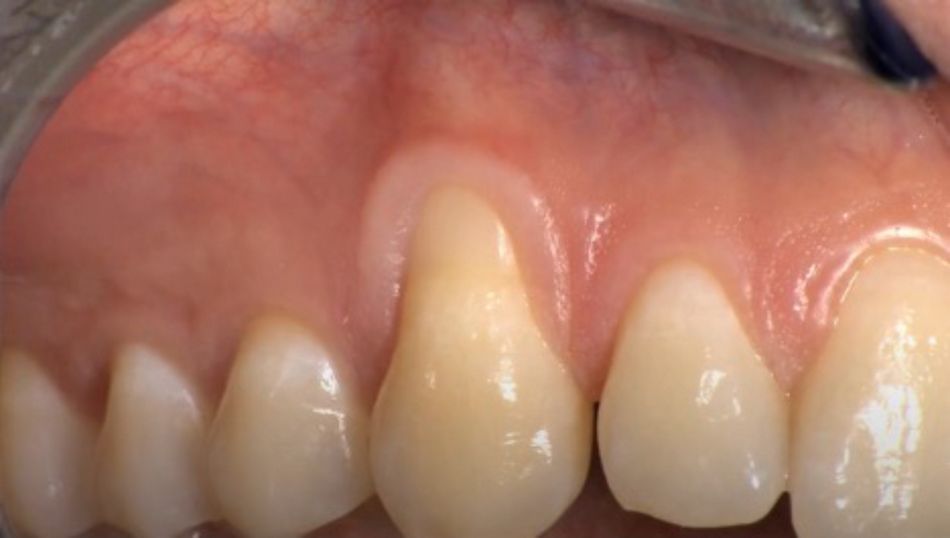

Initial situation: A healthy 34-year-old female patient with no periodontal diseases, presented at the dental clinic with the chief complaint of aesthetic problems due to the exposure during smiling of a root affected by gingival recession.

Treatment: The treatment included a coronally advanced flap (CAF) because there was an amount, even if very small of remaining keratinized tissue (1 mm). The patient’s biotype was thin, and the affected root was buccally displaced. The rationale of using Emdogain® was to improve the quality of the attachment between the newly formed connective tissue and the root surface. By depositing the Amelogenins on the root, Emdogain® promotes the cells of the blood clot to be transformed in cementoblasts and fibroblasts, and this eventually improves the quality of new connective tissue attachment with respect to long junctional epithelium. Another reason why Emdogain® was used, was to improve the soft tissue healing and this is important when the patient has aesthetic requests, as the patient do not want to wait only for the long-term outcomes but short-term results as well. Furthermore, it was decided to add the use of mucoderm® because the objective was not to only achieve root coverage which can be achieved with CAF itself, but also to increase the soft tissue thickness, which is a condition that is a critical for the long-term maintenance of the outcome. In terms of post-operative course, it was optimal. The patient did not have any pain at all, she presented no swelling nor hematoma, and from the first follow-up visit there was a nice adaptation and blending of the treated area.

Treatment outcome: The patient was very happy with the aesthetic outcome and for the complete disappearance of hypersensitivity immediately after the surgery. Moreover, within time the patient was even more satisfied because it was easier for her to perform oral hygiene due to the increase of keratinized gingiva and soft tissue thickness.